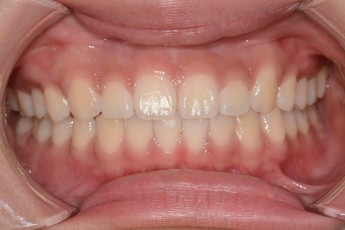

Before

After